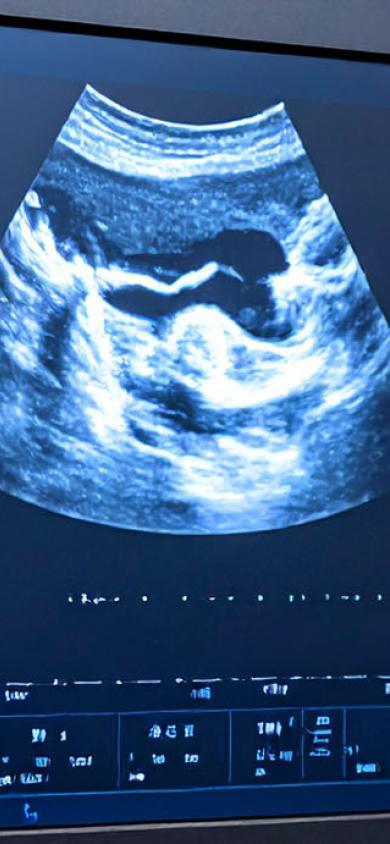

Ultraschalluntersuchung

Mittels einer Sonde (Schallkopf), die ähnlich wie ein Radargerät arbeitet, lässt sich durch die Haut ein sektorförmiges, sich laufend anpassendes Bild anfertigen. Damit ein besserer Kontakt zwischen Haut und Sonde entsteht, wird ein Gel auf den Schallkopf bzw. auf Ihre Haut gestrichen. Mit dieser Methode lassen sich die Oberbauchorgane, das Herz, die Schilddrüse, und weitere Organe besonders gut untersuchen.

Zudem kann eine Flüssigkeitsansammlung im Bauchraum, auf der Lunge, unter der Haut oder im Muskel rasch festgestellt werden. Der Ultraschall ist für den Körper harmlos. Deshalb kann eine Ultraschalluntersuchung bei Bedarf ohne Bedenken wiederholt werden.

Image